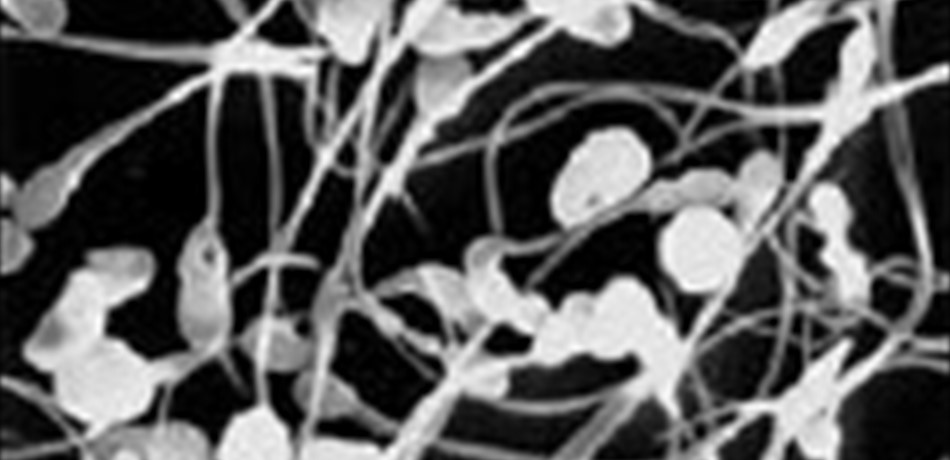

دعت دراسة أميركية حديثة إلى ضرورة تنبه الرجال إلى ما يأكلونه، بعدما تبين أن نوعية اللحوم التي يستهلكونها تؤثر سلباً أو إيجاباً على خصوبتهم. وأجرى باحثون أميركيون دراسات أظهرت أنّ الرجال الذين يكثرون من تناول اللحوم المعالجة مثل النقانق واللحوم المقددة يستجيبون بشكل أقل لعلاجات الخصوبة، مقارنة مع من يأكلون الدجاج أو غيرها من لحوم الدواجن. وأشاروا إلى أن هذه الدراسة تؤكد أن نوعية اللحوم المستهلكة توثر على عملية الإنجاب ولا سيّما على قدرة الحيوانات المنوية على تخصيب بويضة المرأة. وذكَّروا أنّ اتباع نظام غذائي صحي أمر سهل وأساسي من أجل الحفاظ على صحة جهاز التناسل والصحة عامًة. ويشار إلى أن الدراسة شملت 141 رجلاً من أزواج يخضعون لعمليات تخصيب اصطناعية في مستشفى ماساشوستس العام. وتبيَّن أن نسبة نجاح عملية التخصيب كانت أعلى بنسبة 13% لدى الذين يأكلون الدجاج ، مقارنة مع من يأكلون كمية أقل من لحوم الدجاج. ومن ناحية ثانية، كانت النسبة أعلى بـ28% مقارنة مع من يكثرون من أكل اللحوم المعالجة. (